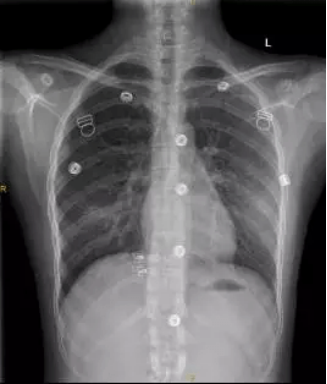

这是一张标准胸片

一张合格的胸片是不允许有任何体外异物的,因为任何异物的存在都会影响诊断。